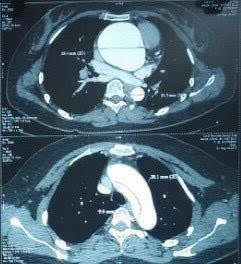

Hình ảnh phồng lóc động mạch chủ trên phim chụp (ảnh nhỏ). Ảnh: BV cung cấp

Hình ảnh phồng lóc động mạch chủ trên phim chụp (ảnh nhỏ). Ảnh: BV cung cấp

Hình ảnh phồng lóc động mạch chủ trên phim chụp. Ảnh: BV cung cấp

Hình ảnh phồng lóc động mạch chủ trên phim chụp. Ảnh: BV cung cấp